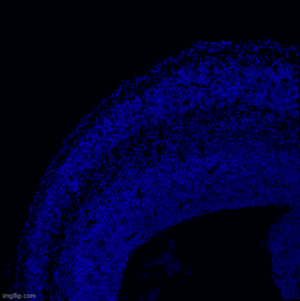

Our lab aims to elucidate the fundamental mechanisms that dictate cell fate acquisition and neuronal maturation during mammalian corticogenesis.

To unravel new regulators of neurodevelopment, we learn from the genetic mutations that have been associated to neurodevelopmental disorders (NDDs), including malformations of cortical development, intellectually disability and epilepsy. Although the etiologies of those diseases are not always clearly understood, the nature of the mutated genes can give us pathological insights and may elucidate general principles for brain development.

1. Translational Control of Neuronal Fate and Identity

The cerebral cortex is a central structure of the mammalian brain, characterized by a remarkable diversity of neuronal types. Understanding the origin of the extraordinary neuronal diversity is fundamental to understanding how the cortical architecture and its diverse functions emerge during development. It remains a critical challenge in cellular and molecular neurobiology. While the efforts have been focused on transcriptional control, evidence for regulation at the translational level is emerging. We hypothesize that translational control, though oft overlooked, acts in a combinatorial fashion with transcriptional induction to regulate gene expression programs during cortical patterning. We have demonstrated an intimate functional link between cortical development and cellular content of mature transfer RNA (tRNAs) (Laguesse et al, Dev cell, 2015, Del-Pozo-Rodriguez, Brain, 2025), the major determinant of translation. We, therefore, propose to address how translational control, through the modulation of the availability of mature translationally competent tRNAs, hones gene expression programs during lineage progression, thereby regulating neuronal diversity. Studying this yet unexplored question could unravel a hitherto unrecognized level of neuronal fate identity determination in the cerebral cortex